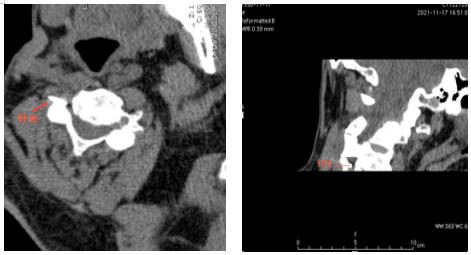

一次偶然的机会,经人介绍,李爹爹来到了91porn 疼痛科二病区就诊,杨庆红主任经过查体后诊断其为带状疱疹性神经痛,疼痛范围为颈丛神经分布区域。李爹爹住院后,医生予以口服普瑞巴林胶囊及泰勒宁止痛,但效果不佳,后进行了超声引导下颈丛神经阻滞,但效果维持时间不长,最终杨庆红主任决定为患者施行CT引导下颈丛神经脉冲射频微创手术。但李爹爹本身是一位肝硬化患者,胸壁静脉及颈部静脉怒张,再加上颈部本身结构复杂,存在多根大血管,容易引起出血。

为了确保手术安全顺利进行,术前杨庆红主任组织科室充分讨论病例,制定了详细的手术方案。11月21日,在放射科主管技师胡卫的协助下,杨庆红主任带领疼痛科医生李圣洪在CT引导下找准穿刺路径、角度及深度,为李爹爹实施了颈丛神经脉冲射频微创手术,术后当晚,李爹爹就感觉疼痛明显缓解,人也轻松了一大截。目前患者疼痛控制良好,几乎没有疼痛,预计本周内出院。